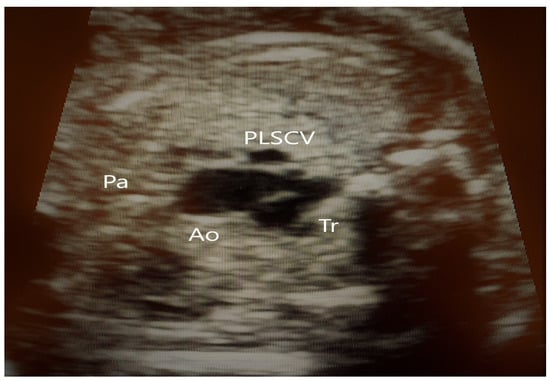

4.2. Case 2

4.3. Case 3

4.4. Case 4